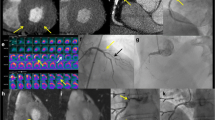

The strength of perfusion imaging is visualizing the myocardial blood flow on which myocardial metabolism depends. Perfusion MR uses similar concept used in nuclear perfusion imaging or perfusion cardiac magnetic resonance imaging (CMR). From the myocardial and left ventricular cavity arterial input function or time-attenuation curves, the extent of regional myocardial perfusion is calculated or compared with the other regional myocardial perfusion. Perfusion is imaged in a complete cardiac cycle (dynamic perfusion imaging) or as a snapshot (static perfusion imaging). Scanners equipped with dual energy source can be used for perfusion imaging and mostly used for static perfusion imaging (Fig. 31.2). The performance of perfusion CT for predicting functionally significant stenosis is considered to be similar to nuclear perfusion imaging, stress CMR, or stress echocardiography, and is being validated against FFR [3,4,5]. Standard coronary angiography can be done along with perfusion imaging, which enables simultaneous anatomic evaluation of coronary arteries with functional evaluation of heart. Therefore, perfusion CT combined with coronary CT angiography can be a one-stop shop modality that assesses both anatomical and functional stenosis within a single session [6].

Principle of myocardial perfusion CT . The difference between myocardial blood flow correlates with the myocardial up-slope normalized by arterial input function (AIF) up-slope, area under curve (AUC) of myocardial signal intensity up to AIF peak, or myocardial peak signal intensity. The difference between normal tissue and ischemic tissue is imaged as perfusion defect (line with red arrows)

The most important limitation of non-invasive physiological assessment is radiation exposure required by CT image, especially in perfusion CT imaging. A combined rest and stress myocardial perfusion CT may reach radiation dose of >15 mSv. Although the radiation exposure of CT is regarded as lower than those with nuclear imaging, appropriate radiation reducing strategy should be applied as reasonable as possible (Fig. 31.7).

Insufficient spatial and temporal resolution is the major cause of inadequate results. Typical isotropic spatial resolution of CT image is 0.5 mm at best. Therefore even single voxel difference in 3.0 mm sized vessel results in 17% difference in diameter. Such vessel with 50% diameter stenosis would have just 7–9 voxels in the lumen. Addition or deletion of single voxel causes 33% difference in minimal luminal diameter or 11% difference in minimal luminal area (Fig. 31.8 ). Mathematical correction by subvoxel resolution technique and avoidance of partial volume effect is being developed.

Limitations in spatial resolution and motion artifact. (a) Less than 10 voxels consists lumen of typical coronary artery disease with 3.0 mm diameter and 50% stenosis. Omission or addition of single voxel affects significantly the result of computational FFR. (b) The limitation of spatial resolution may be worsen by the motion artifact

Single measurement or modality may represent but cannot show every aspect of coronary artery disease and is not sufficient for decision of treatment strategy. Revascularization by percutaneous coronary intervention or bypass surgery relieves symptom but does not improve clinical outcome of all patients [67]. Non-invasive physiological assessment may vastly improve the predictive value of coronary artery disease evaluation and be additive to the current decision-making strategy (Fig. 31.9).